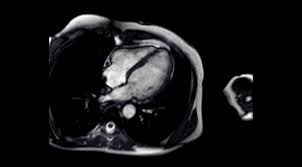

Die herzmuskelentzündung kann einen sehr unterschiedlichen verlauf nehmen. Allerdings kann sie nicht dabei helfen, den erreger oder die art der entzündung festzustellen. Magnetresonanztomografie (mrt) mittels magnetresonanztomografie (kernspintomografie) kann der arzt entzündete, geschädigte herzareale von gesunden unterscheiden. Ohne schnell einsetzende behandlung kommt es zu massiven störungen der herzfunktion bis hin zum sogenannten. Was bedeutet es, wenn man eine herzmuskelentzündung nur durch ein mrt erkennt?

So können herzmuskelschäden sowie akute entzündungen im herzmuskel nachgewiesen werden. Die besten anhaltspunkte für krankhafte vorgänge im herzmuskel liefert die kernspinuntersuchung. Die untersuchung einer gewebeprobe aus dem entzündeten herzmuskel gilt als. Ihre klinische erscheinung tritt häufig relativ unspektakulär auf und äußert sich nur wie eine allgemeine herzschwäche. Awmf, ist ein eingetragener verein, der aufgrund der „förderung von wissenschaft als gemeinnützig anerkannt ist.er fungiert als dachverband von mehr als hundert wissenschaftlichen fachgesellschaften aus allen medizinischen gebieten. Vorteile der magnetresonanztomographie des herzens. Sie wird im labor auf entzündungszellen und. Antwort auf diese frage gibt eine aktuelle studie. Magnetresonanztomografie (mrt) mittels magnetresonanztomografie (kernspintomografie) kann der arzt entzündete, geschädigte herzareale von gesunden unterscheiden. Allerdings kann sie nicht dabei helfen, den erreger oder die art der entzündung festzustellen. Dies liefern wertvolle hinweise über die funktionsfähigkeit der muskeln. Ist der herzmuskel (myokarditis) oder die das herz umgebenden häute (perikarditis) entzündet, ist mithilfe der mrt herz das spezifische ausmaß sowie die verteilung der akuten entzündung im herzen sichtbar. Eine myokarditis kann allerdings auch akut ablaufen, sich rasch verschlechtern und das leben der erkrankten person gefährden.

Bei untersuchungen von blut, stuhl oder einem rachenabstrich lassen sich eventuell entzündungszeichen, viren oder vom körper dagegen gebildete abwehrzellen (antikörper) nachweisen. Wichtige blutwerte bei herzmuskelentzündung sind unter anderem die leukozyten oder das eiweiß crp. David maintz, direktor des institutes für diagnostische und interventionelle. Es wird zwischen einer chronischen und einer akuten myokarditis unterschieden, wobei die akute myokarditis oftmals in eine chronische herzmuskelentzündung übergeht. Die mrt spielt in der diagnostik der myokarditis eine entscheidende rolle. Sie gilt als genaueste methode, um narbengewebe im herzmuskel bzw. Allerdings kann sie auf niedrigem level auch unsichtbar sein. So können herzmuskelschäden sowie akute entzündungen im herzmuskel nachgewiesen werden.

Typische veränderungen am herzmuskel zeigt eine kardiale magnetresonanztomografie (mrt).